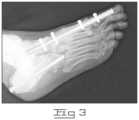

FIG.3 is an x-ray picture taken following an experimental procedure to insert an implant into a patient's foot.

FIG.3 is an x-ray picture taken following an experimental procedure to insert an implant into a patient's foot with two fasteners at both the proximal and distal ends. The procedure, performed in March of 2000, is being followed-up to determine the effectiveness of the newly adapted treatment. This is the only procedure to date ever performed of its kind. Such a procedure is an embodiment of the present invention.

The implant was a small intramedullary (Smith & Nephew) nail intended for insertion in a longer bone. The fasteners were locking screws inserted into the transfixation holes and also into the talus and first metatarsal bones. Such a device is an embodiment of the present invention.